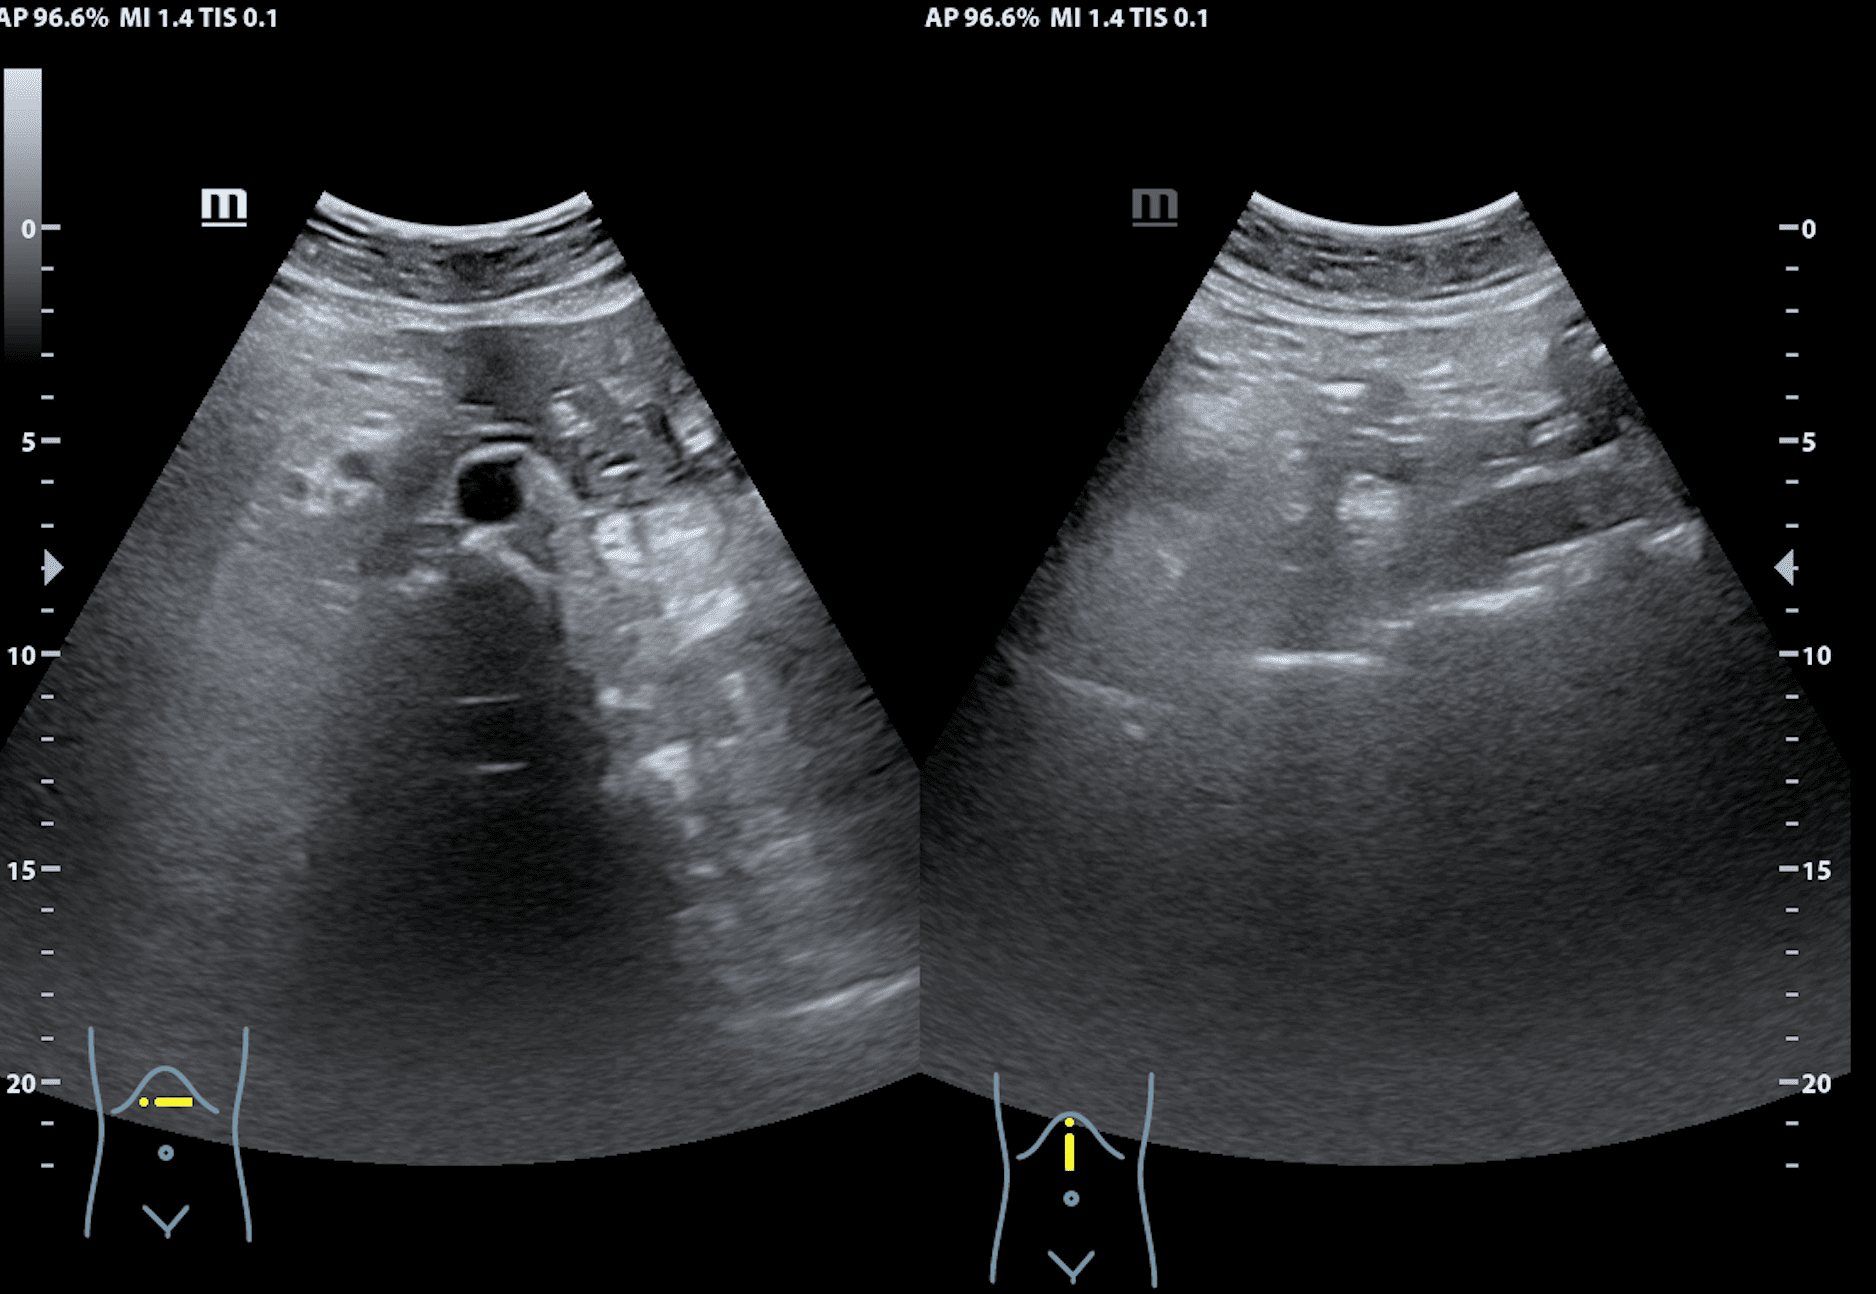

Hallazgos ecográficos

Hepatomegalia y esplenomegalia de 21,03 cm. Adenopatías retroperitoneales.